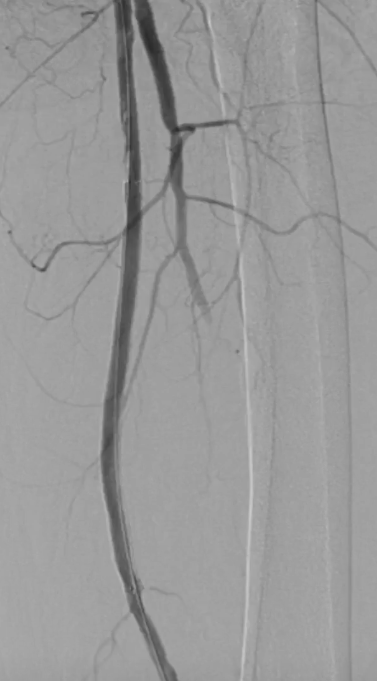

栓塞处理:造影发现管腔获得尚可,但是流速明显较慢,考虑保护伞上方管腔闭塞(考虑斑块/血栓脱落),用6F导管反复抽吸后收回保护伞。

夹层发现及处理:

更换V18导丝后造影显示,胫后动脉血流通畅,胫前动脉疑似仍有小的血栓脱落,导致栓塞。

股浅动脉全程管腔获得尚可,但中段有明显的夹层形成,

先用5mm长球囊充分预扩张;再次造影显示,股浅动脉近中段管腔获得良好,中远段仍有大量的夹层

采用药物涂层球囊(DCB)对股浅动脉病变段全程覆盖:近端用5-250新型药涂球囊,远端用5-150 impact 药涂球囊;

造影显示中段仍有局限性夹层,为保证远期通畅率,植入补救性支架并以5mm球囊后扩张